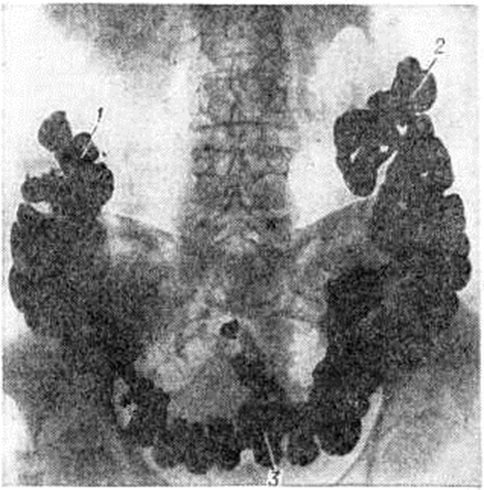

Рис. 3.

Рентгенограмма брюшной полости больного с колоптозом (прямая проекция) после перорального контрастирования толстой кишки: печеночный (1) и селезеночный (2) изгибы ободочной кишки расположены низко, поперечная ободочная кишка (3) провисает в малый таз.

При опущении толстой кишки определяется низкое положение печеночного и селезеночного её изгибов, а также слепой и поперечной ободочной кишок. При этом чрезмерно подвижная слепая кишка может находиться в малом тазу, куда нередко провисает и имеющая вид гирлянды поперечная ободочная кишка (рисунок 3). Рельеф слизистой оболочки остаётся нормальным. Смещаемость кишки при отсутствии спаек не нарушена. В опущенной и удлиненной кишке могут наблюдаться дополнительные петли, перегибы, повышение или понижение тонуса, замедление пассажа содержимого. Задержка контрастного содержимого может достигать 96 часов и более. Опущение отделов кишечника необходимо дифференцировать с их вторичным смещением, обусловленным объемным или рубцово-спаечным процессом в брюшной полости или забрюшинном пространстве.